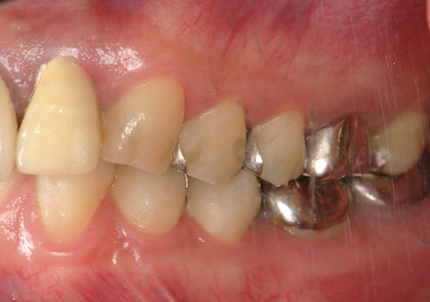

患者:S.G様(55歳/男性)

初診日 :2014年6月10日

主訴 :義歯が嫌いで使わず奥歯が咬めないので、全体の治療を希望する

1.初診時口腔内写真(2014年6月)